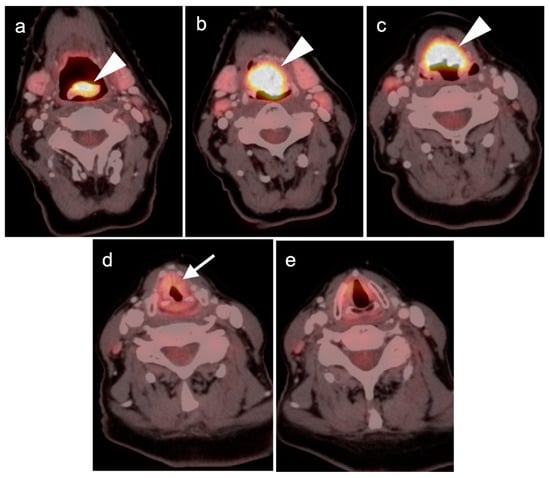

2.2. Squamous Cell Carcinoma of the Head and Neck (SCCHN)

- Laryngeal squamous cell carcinoma

- Glottic larynx